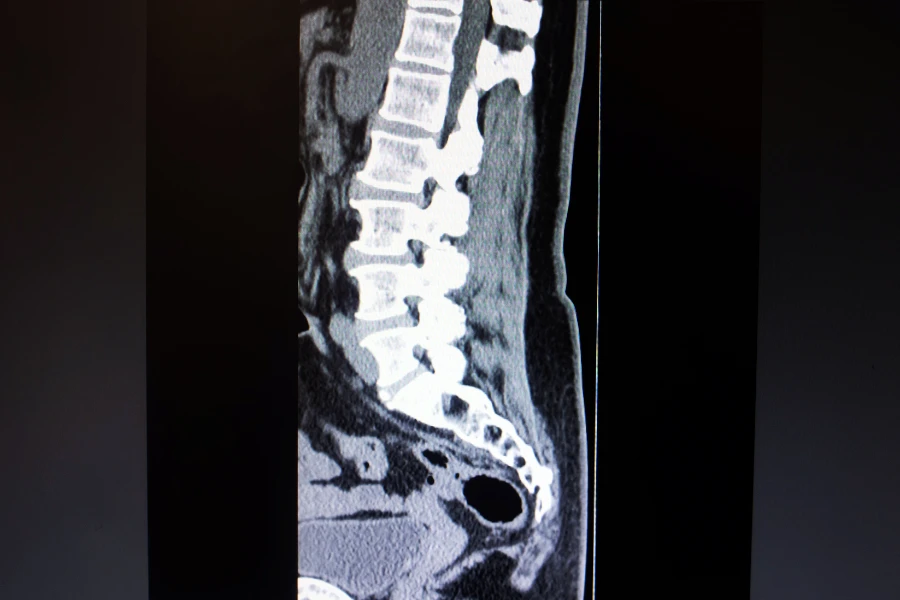

Intervertebral discs act as shock absorbers between the vertebrae. A herniation occurs when the inner gel-like nucleus protrudes through the outer fibrous ring, potentially compressing nearby nerve structures.

Why MRI must be interpreted carefully

MRI is an indispensable diagnostic tool, but it is frequently misunderstood.

Disc protrusions are often found in asymptomatic individuals, especially after the age of 40. Treating MRI images instead of patients leads to unnecessary procedures.

A neurosurgeon evaluates:

- the level and type of herniation;

- degree of neural compression;

- spinal canal dimensions;

- correlation with neurological examination.